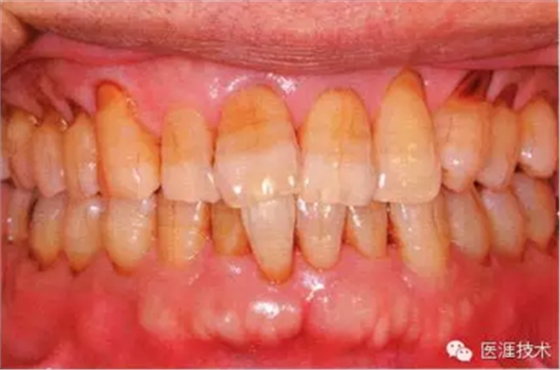

55歲牙周炎男性的臨床照片

55歲男性抽煙患者(1天20支、抽煙35年)。菌斑控制得不好。通過(guò)牙周探診,全頜有4~9mm的牙周袋,有1~3度的根分叉部病變。通過(guò)X光片觀察,上頜前牙中度牙槽骨吸收,其他地方有中度牙槽骨吸收。受吸煙影響,牙齦纖維性肥厚,呈紅黑色。牙齦幾乎沒(méi)有浮腫和發(fā)紅,所以這個(gè)病例是從外觀上無(wú)法預(yù)測(cè)病癥嚴(yán)重程度的病例。